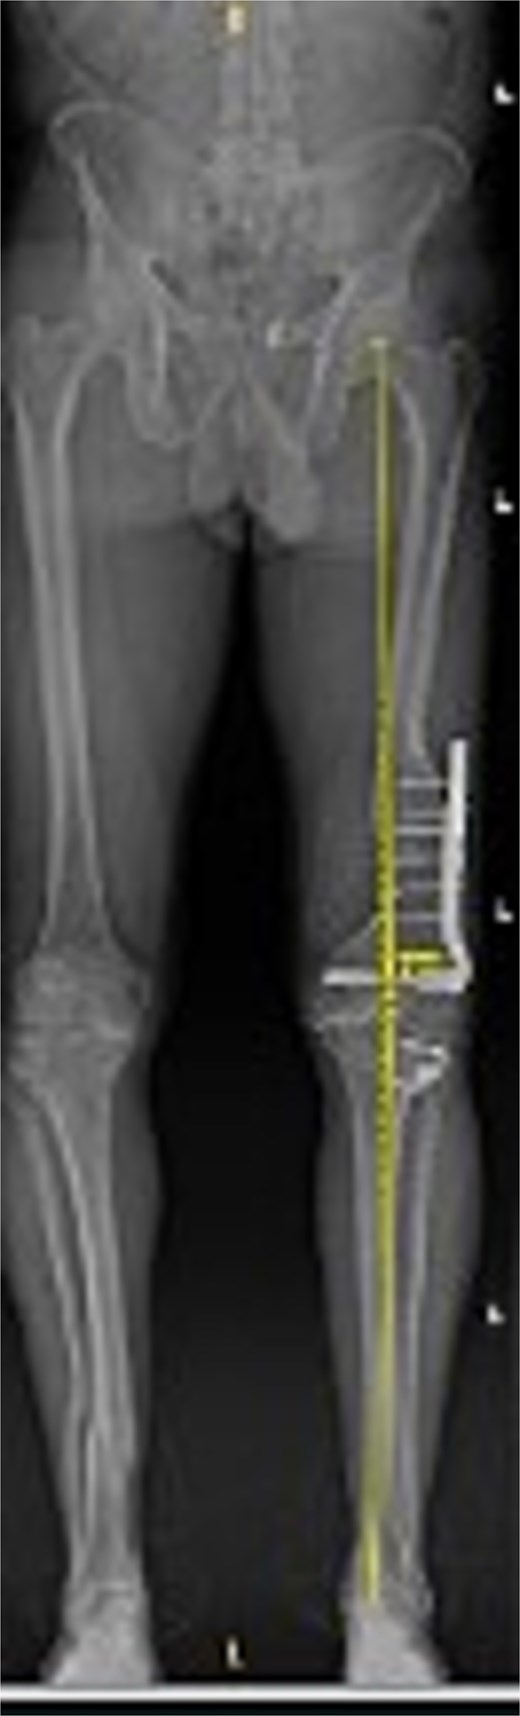

Preoperative standing AP radiograph of the patient’s lower extremities. The left femur has a lateral plate from a prior fracture. There is 3° varus alignment of the arthritic left knee. The femoral deformity is primarily in the sagittal plane, and the retained hardware is visible.

Figures 3 and 4 show a postoperative lateral and AP radiograph of the left knee. The patient was able to fully extend his knee after surgery and instructed to weight bear as tolerated until his two-week follow-up. Patient-reported outcome measures were completed at 2 year follow up (Table 1) with no reported complaints or issues at that time.

Postoperative AP bone length films 1 year after robotic-assisted TKA with hardware retention. The new femoral and tibial components are in place. The retained femoral plate is visible along the lateral cortex of the femur. Postoperative mechanical alignment of the left leg is 0.7°.